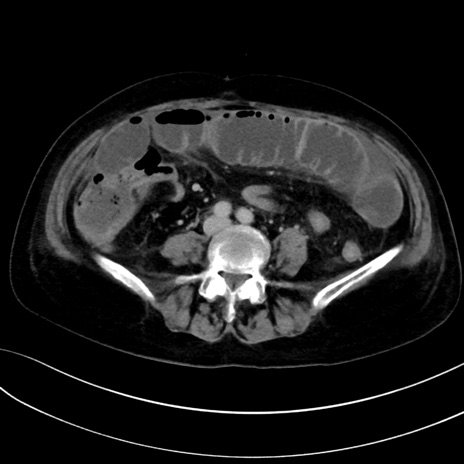

症例13 CT(横断像)1日半後